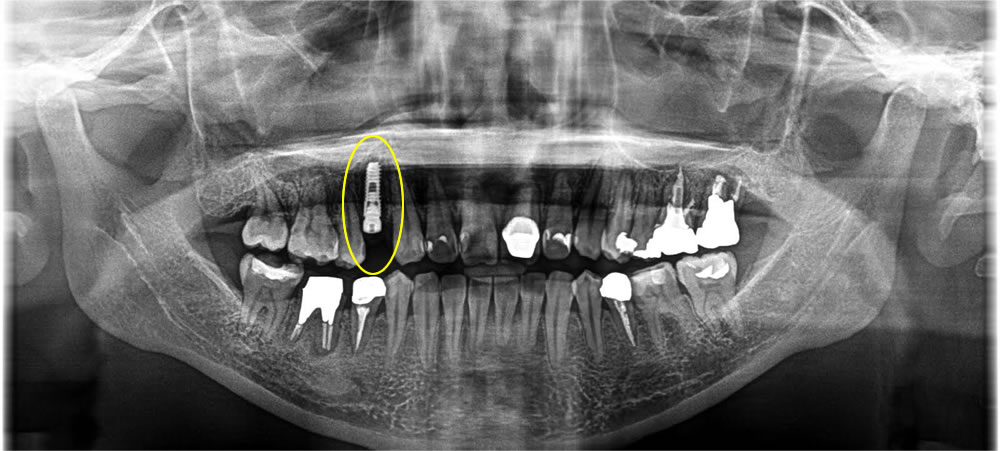

まず歯を抜いたところ、骨の横が感染により吸収されて大きく穴が空いてしまっていました。抜歯窩にインプラントを埋入し、骨を作る処置(骨造成)を行いました。

横の穴が空いてしまっている部位までしっかりと骨を作るため、歯茎を剥離しメンブレン膜でその部分まで覆っていきました。その後、特殊な縫い方で傷口を閉鎖しました。

4ヵ月待ち、インプラントが骨と結合しているのを確認し、上部の歯を作成しました。結果、歯肉もほとんど退縮する事なく綺麗に歯を作る事ができました。